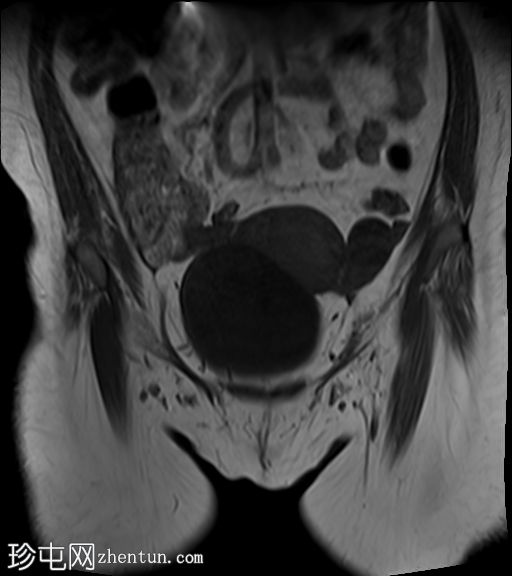

冠状位

T2加权像

子宫体积增大,宫底可见息肉样病变,T2加权像呈异常中高信号强度。病变可见轻度扩散受限,增强后呈均匀强化。病变与宫底交界区之间可见一界限清晰的异常高T2信号区域,可能为囊性变性。未见病变超出交界区。

在剖宫产切口远端的前壁上,可见另一处类似的较小病灶。

左侧附件囊性病变,T1加权像信号异常低,T2加权像信号异常高。无增强扫描强化。

子宫内膜息肉是子宫内膜组织的结节状突起。通常表现为T2加权像信号异常高,增强扫描后呈均匀强化。

病理检查通常显示增生期子宫内膜紊乱。